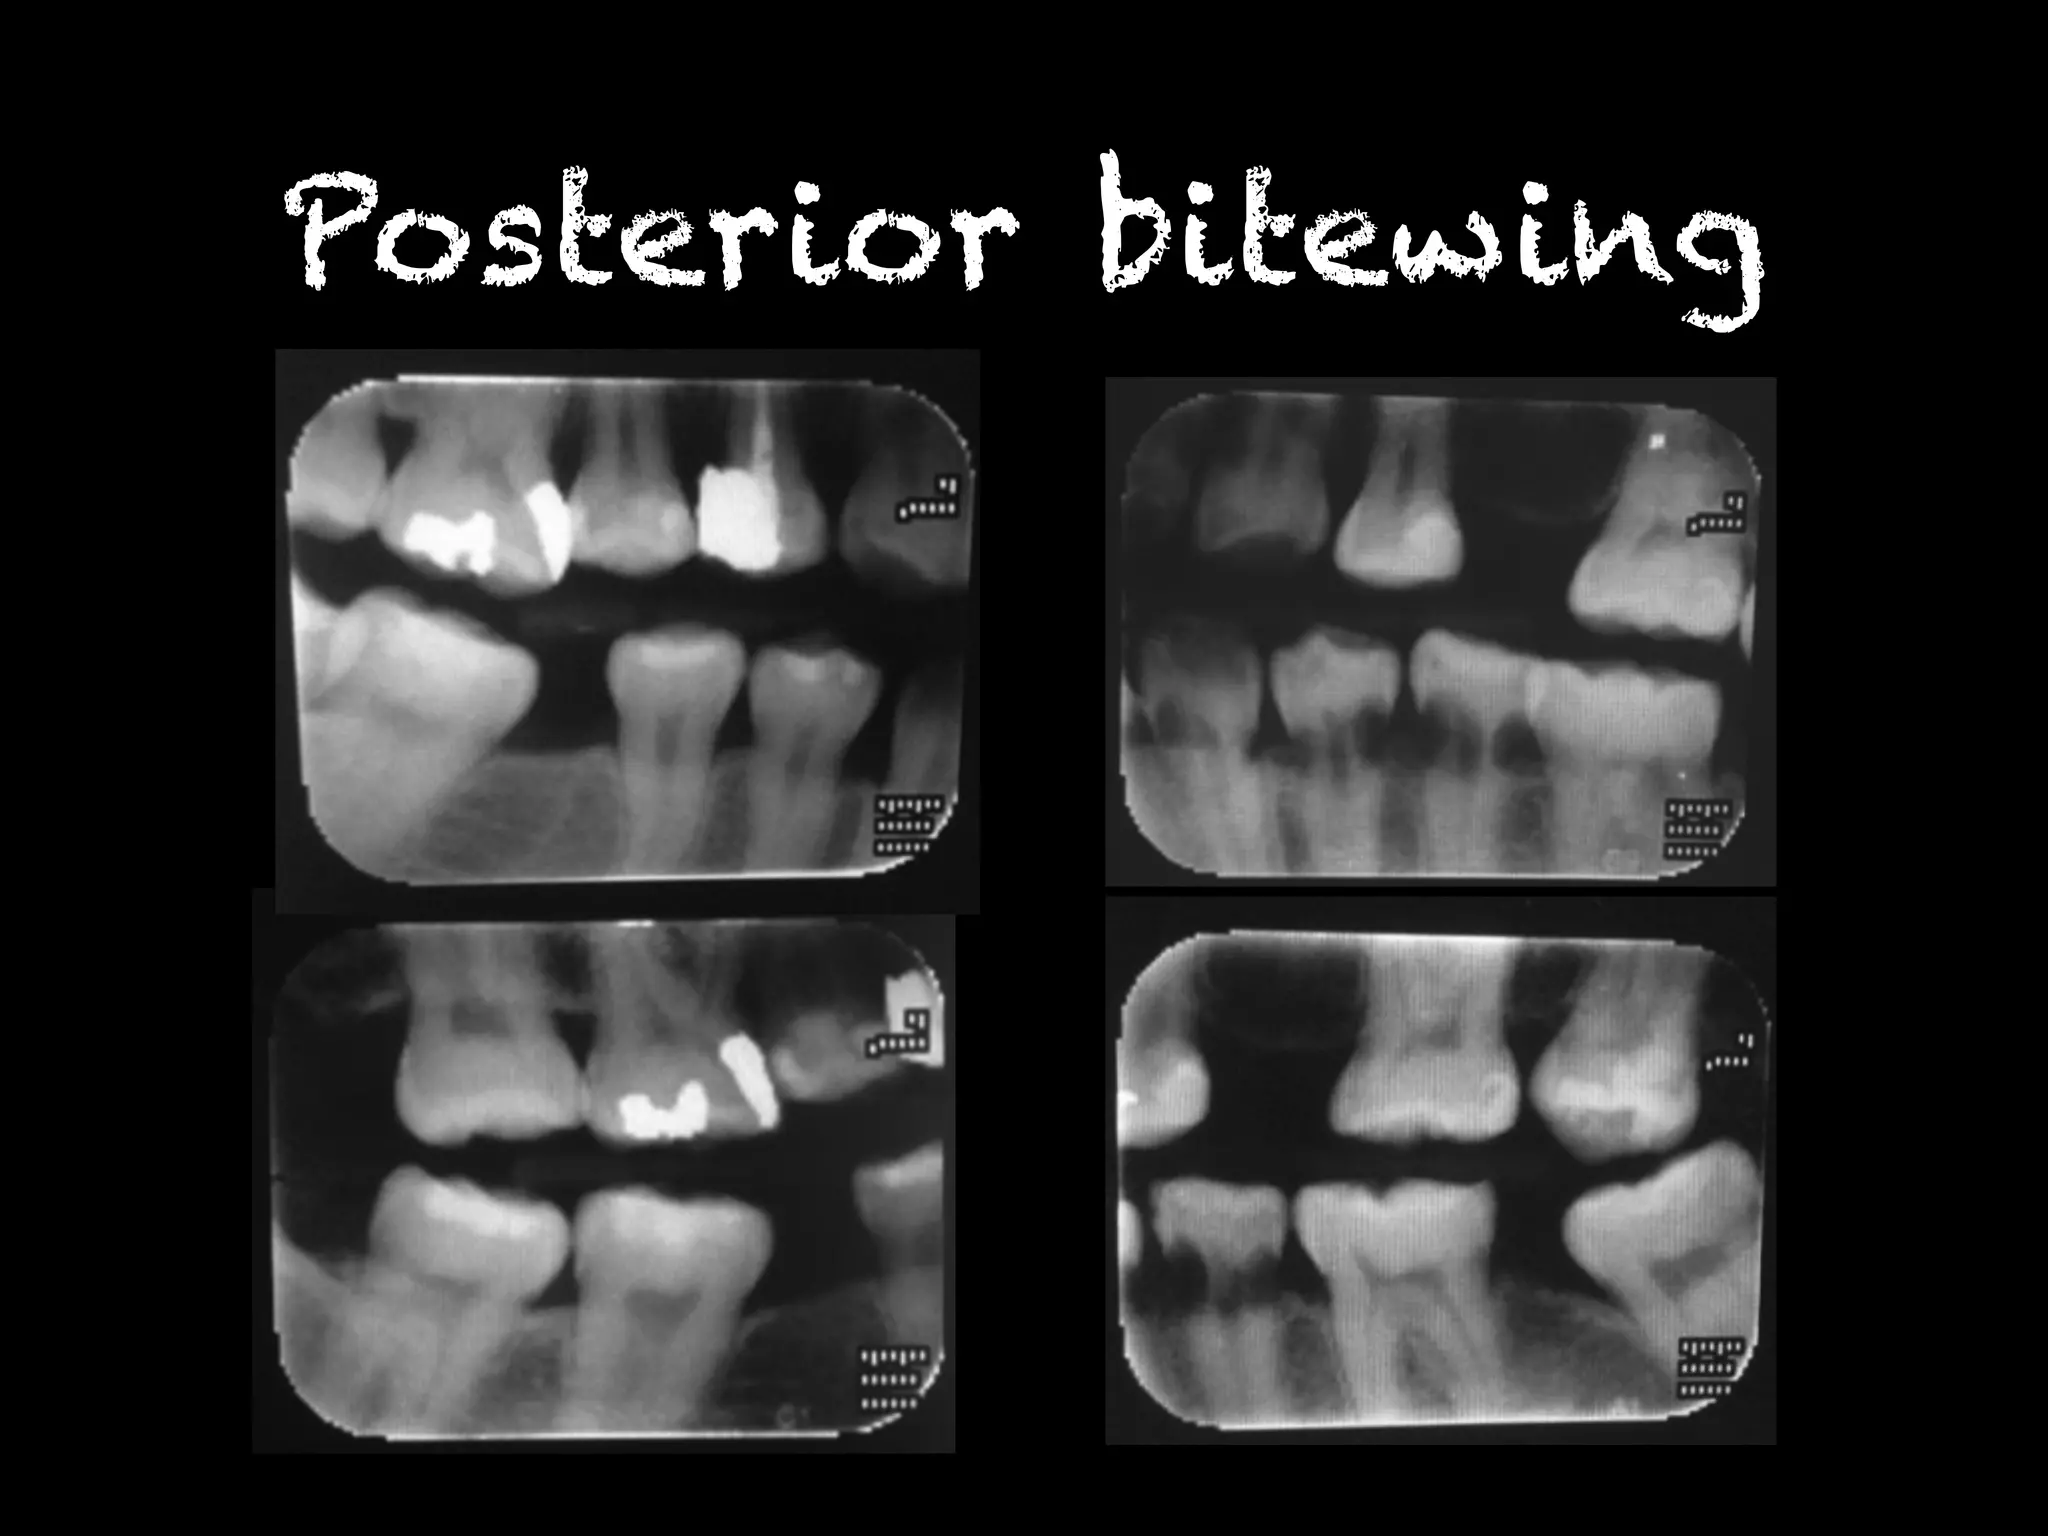

Posterior bitewing

พบรอยโรคโปร่งรังสีที่บริเวณคอฟัน ฟันซี่

12MD,13M,22MD,23M,31MD,32MD,33MD,

41MD,42MD,43MD,34MD,35MD,36MD,

48M

Radiographic finding พบรอยโรคโปร่งรังสีที่บริเวณคอฟันฟันซี่ 12MD,13M,22MD,23M,31MD,32MD,33MD, 41MD,42MD,43MD,34MD,35MD,36MD, 48M